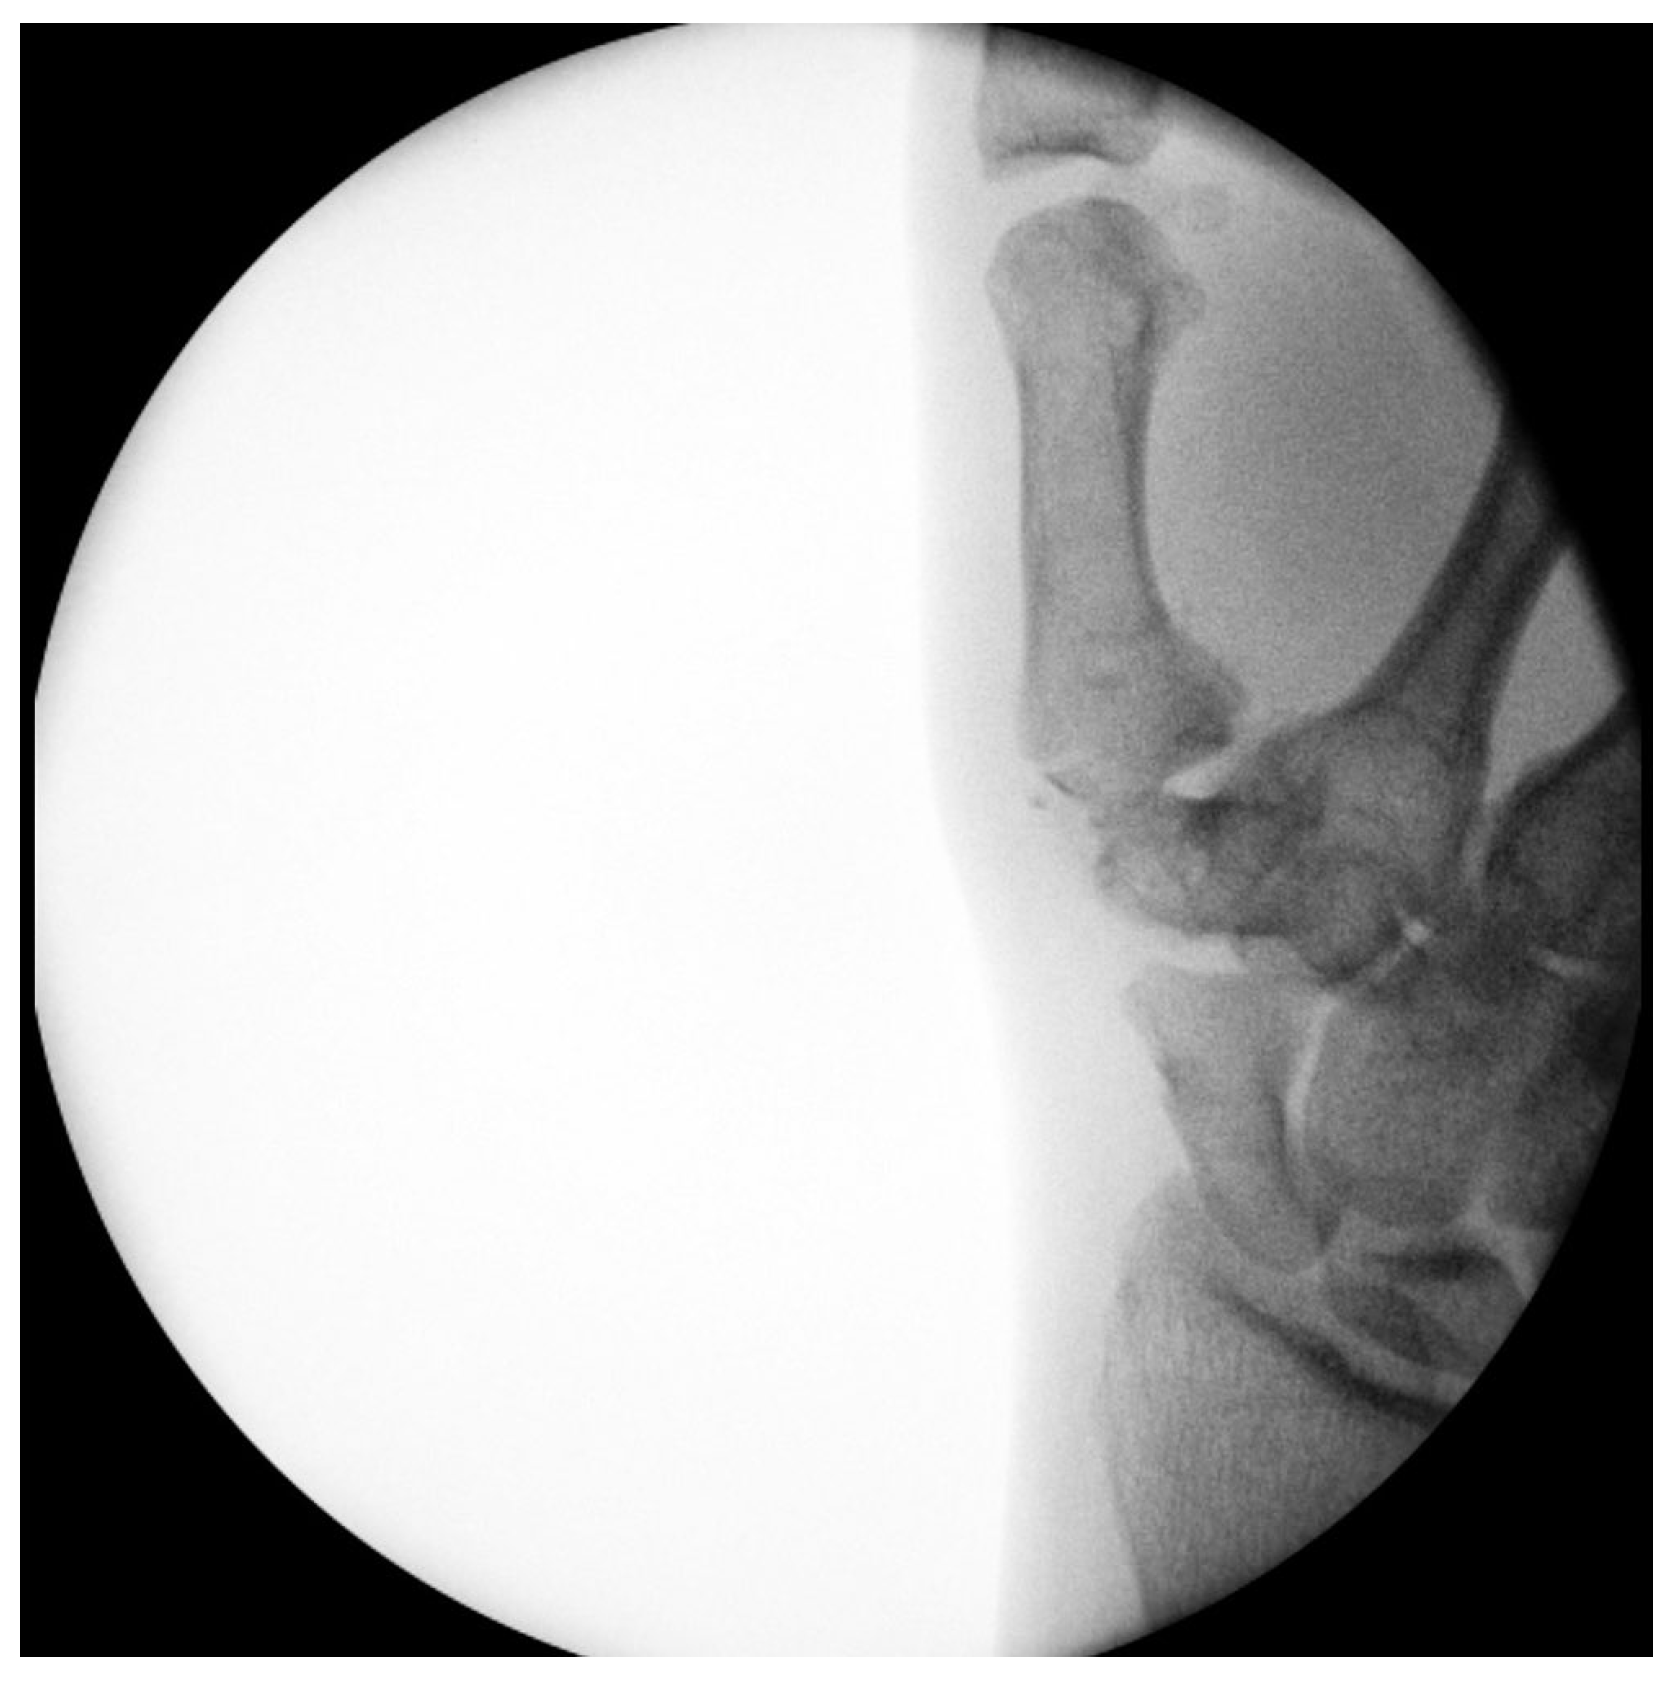

Primary Trapeziometacarpal (TMC) Arthroplasty for Bennett Fracture in Setting of Severe Thumb Osteoarthritis: A Case Report

2. Case Report